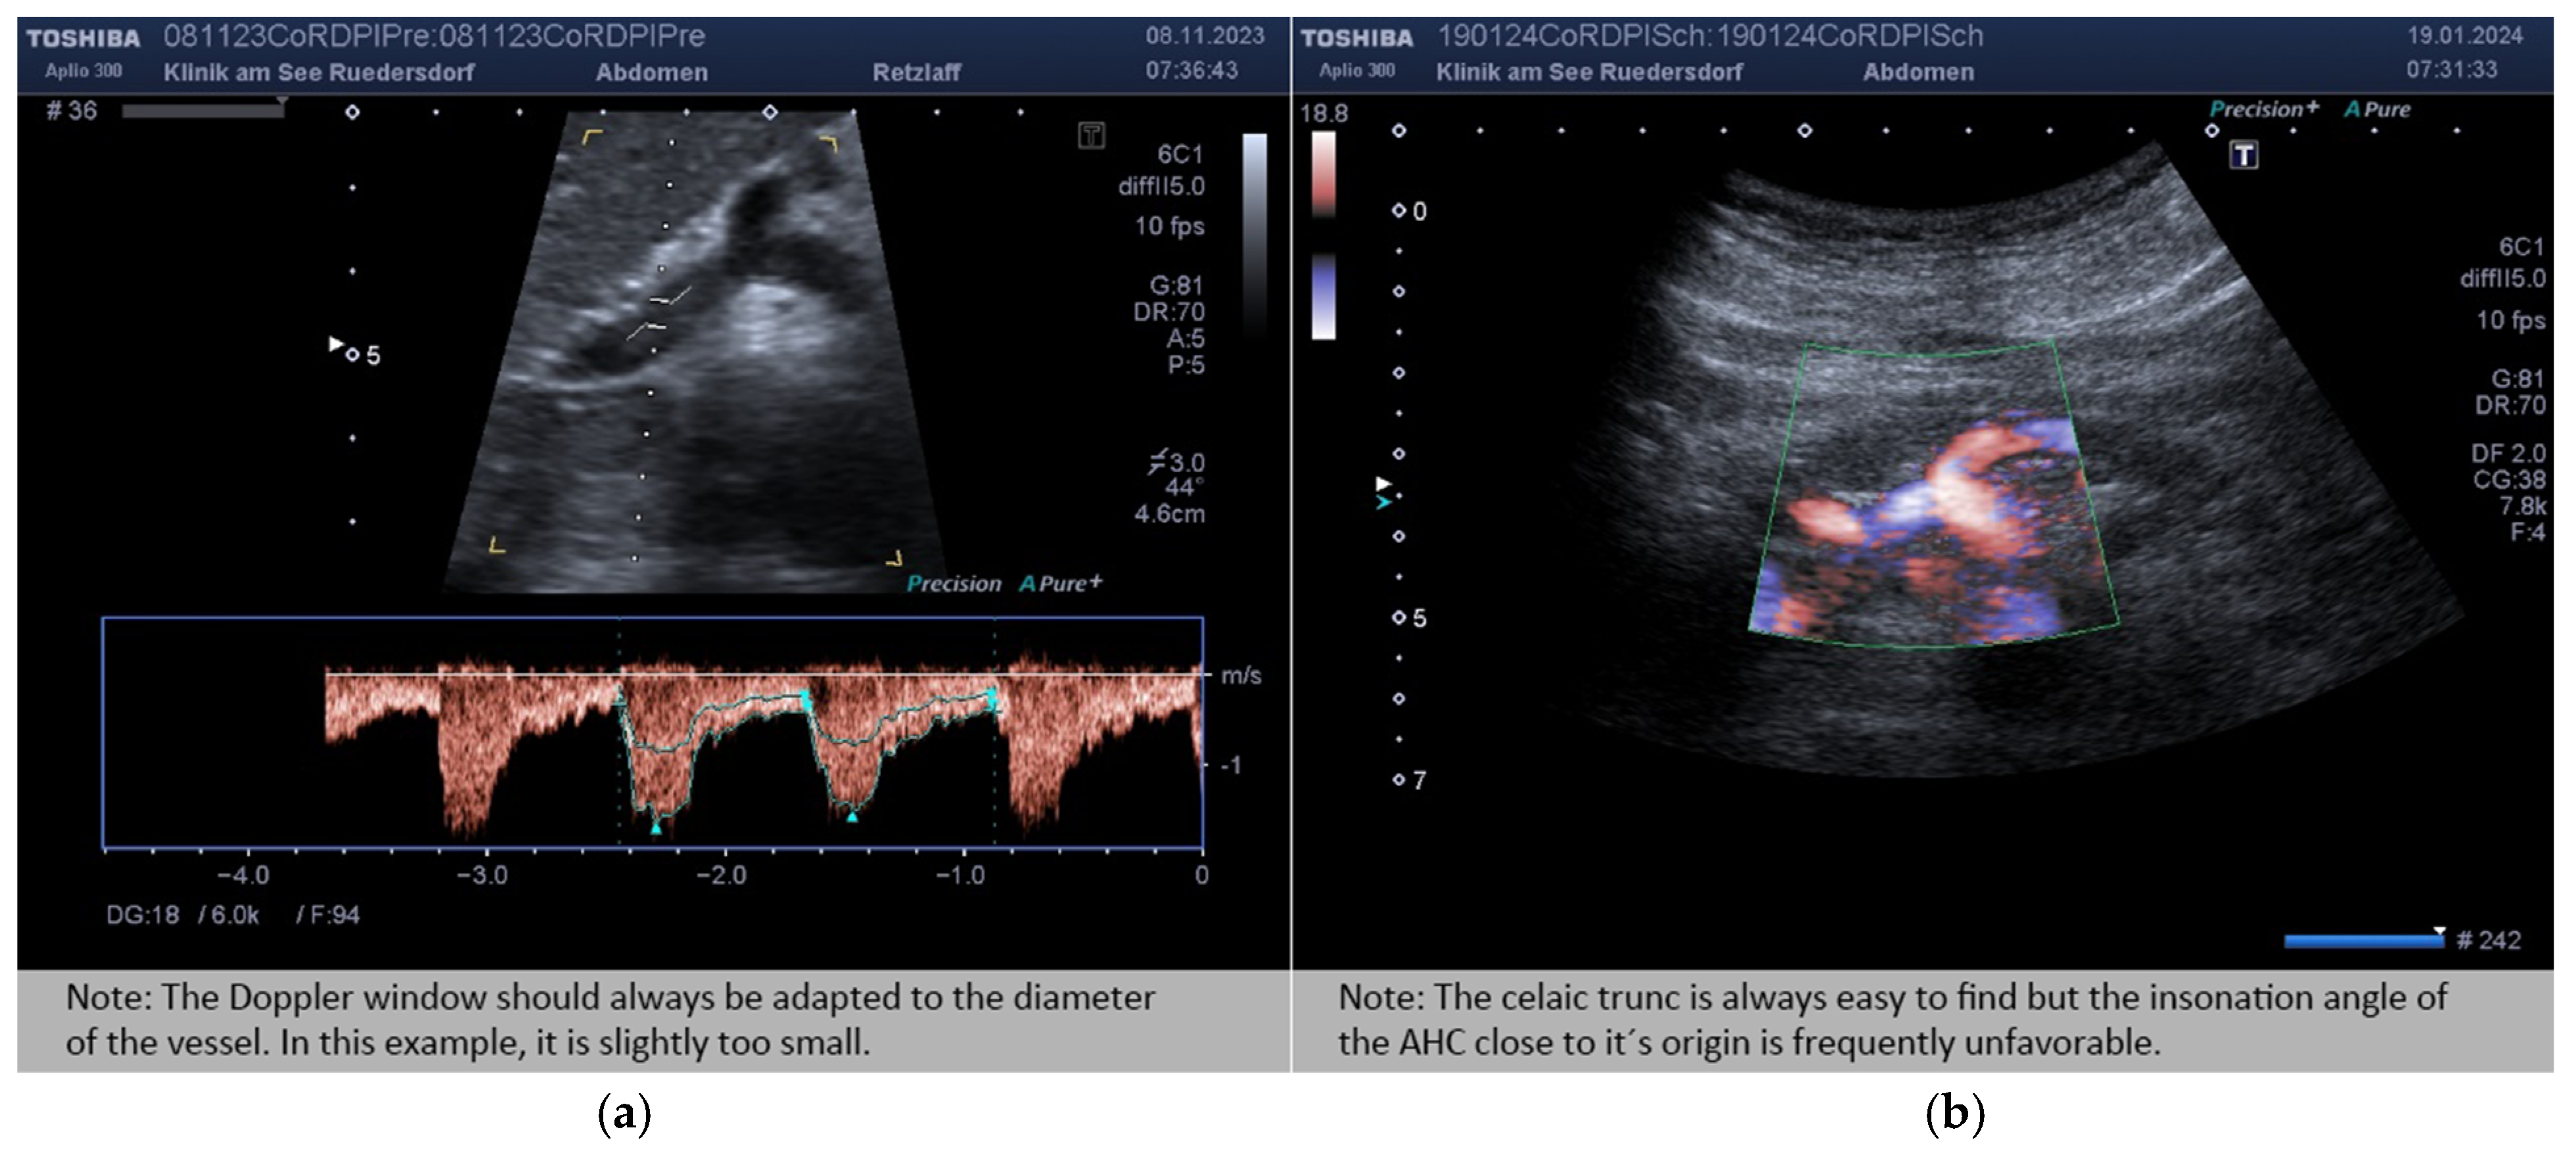

2.3.1. Determination of Vessel Diameter

2.3.2. Location of the Probe, Insonation Angle, and Doppler Window